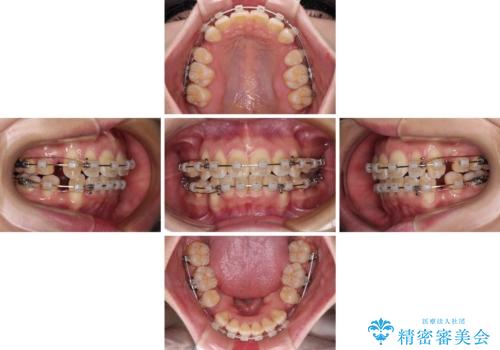

- クリアブラケット

- 2年

- 前歯の出っ歯と口元の閉じにくさを気にして来院された患者様です。

口元を積極的に引っ込めるために、上下左右の小臼歯4本を抜歯し、目立たないワイヤー装置にて矯正治療を行うこととしました。